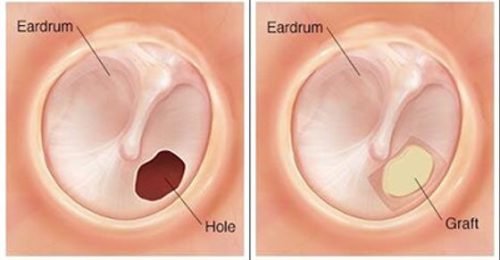

If you’ve been struggling with hearing loss, ear infections, or a perforated eardrum, Endoscopic Minimally Invasive Tympanoplasty may be the advanced solution you’re looking for. As an experienced ENT surgeon practicing in Delhi for over 10 years, I specialize in this cutting-edge, patient-friendly technique that offers excellent results with minimal discomfort and quicker recovery.

Endoscopic tympanoplasty is a modern surgical procedure used to repair a perforated eardrum (tympanic membrane) using a high-resolution endoscope. Unlike traditional microscopic surgery, this approach does not require large incisions or postauricular cuts. Instead, the entire procedure is done through the ear canal, making it truly minimally invasive.

No external incisions – No visible scars, as the surgery is done entirely through the ear canal.

Faster recovery – Patients usually experience quicker healing and less post-operative pain.

Improved visualization – The endoscope provides a wide-angle, high-definition view of the middle ear for more precise surgery.

High success rate – Proven outcomes in restoring hearing and closing eardrum perforations.

Ideal for children and adults – Especially effective in younger patients where minimal trauma is preferred.

Endoscopic tympanoplasty is revolutionizing how ENT surgeons treat middle ear conditions. By avoiding large cuts and improving surgical access, it offers a safer, faster, and more comfortable experience for patients. As someone trained and experienced in this advanced technique, I ensure personalized care tailored to each patient’s condition.

If you’re seeking a trusted ENT surgeon in Delhi for endoscopic tympanoplasty, my clinic ENT care clinic offers state-of-the-art care with a focus on patient comfort and optimal outcomes. Book a consultation today to learn how this minimally invasive ear surgery can help restore your hearing and improve your quality of life.